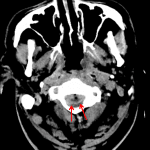

- Incompletely imaged peripherally enhancing ventral epidural collection with intermixed small locules of gas at the level of C1

No acute intracranial abnormality. Incompletely imaged peripherally enhancing ventral epidural collection with intermixed small locules of gas at the level of C1 which is concerning for epidural abscess. Recommend C spine MRI with and without contrast for further evaluation.